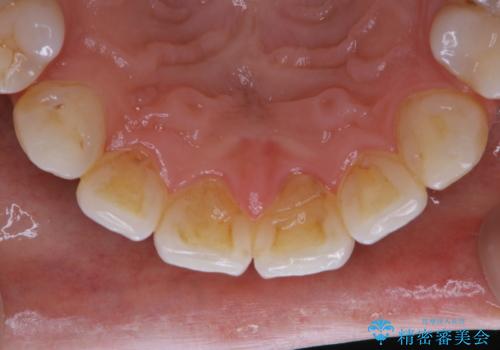

- フロスが以前よりも通りずらくなり、クリーニングしてほしいとのことでした。歯科医院でのクリーニングは3年ぶりとのことです。PMTC60分コースを行いました。

歯科医院で行なわれる専門家による徹底した歯面清掃をPMTC(Professional Mechanical Tooth Cleaning)といいます。専用の機器とフッ化物入り研磨剤を使用して、歯みがきで落とせない歯石や磨き残したプラークを中心に総ての歯面の清掃と研磨を行ない、齲蝕や歯周病になりにくい環境を整えます。

歯石が溜まると、歯と歯の間が埋め尽くされてしまい、デンタルフロスが通りずらくなったり、通せなくなります。

かなり上手に磨ける人でも、セルフケアだけで、虫歯や歯周病予防を行うことには限界があります。